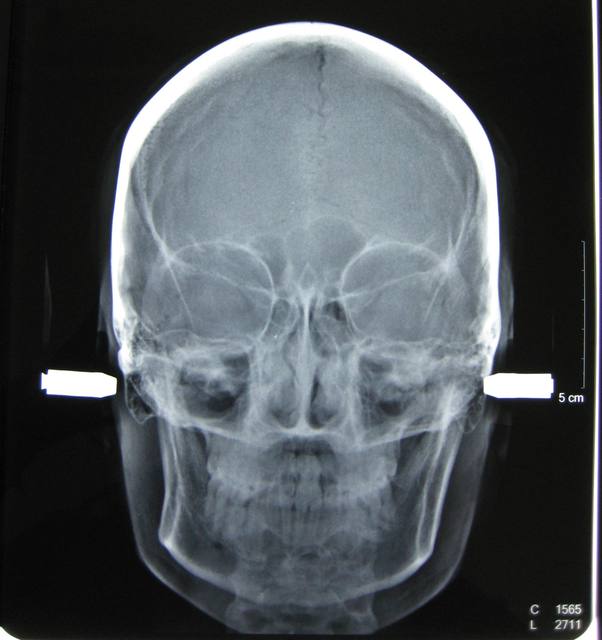

J'ai une patiente de 14 ans qui présente une full classe II due à un maxillaire en proposition car sur une base du crâne trop longue en antérieur. Le maxillaire a une longueur normale.

Voici les photos, radios et moulages du cas

Le maxillaire n'est pas si avancé que cela, par rapport a mac namara ( mais c'est normale, si c'est la base du crane qui est augmenté ) : donc : chirurgie pour raccourcir la base du crane ?

Sinon, extraction 14 24, c'est quand même moins lourd qu'un Lefort.

Merci d'envoyer les photos de face et de profil ..